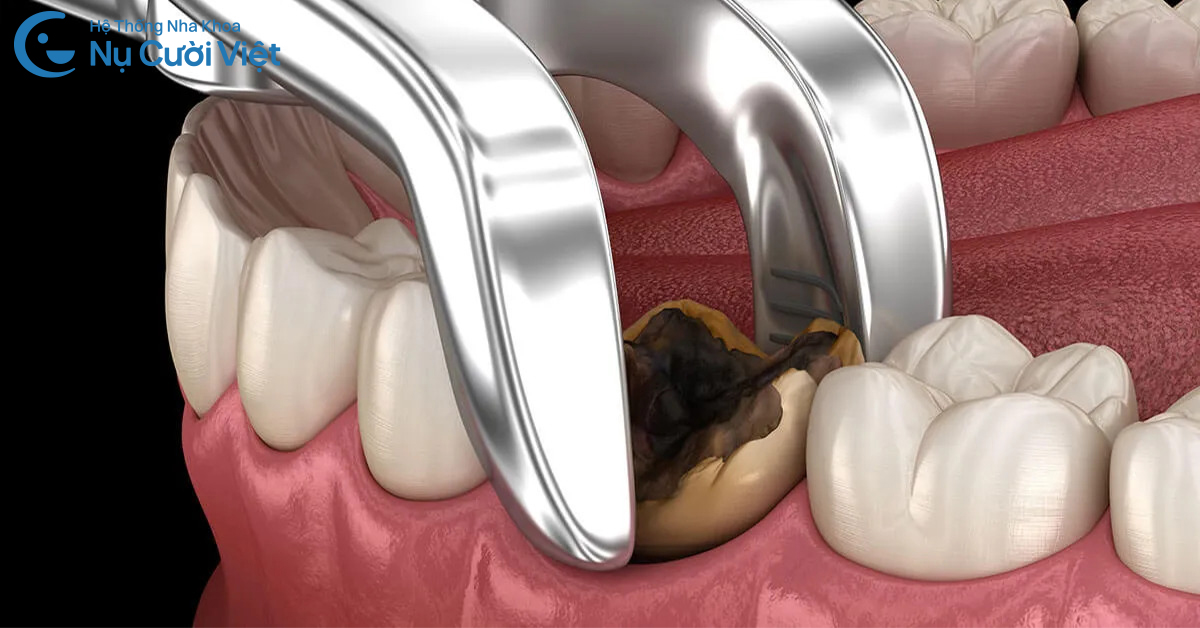

Sâu răng hình thành khi vi khuẩn trong khoang miệng phân hủy đường và tinh bột, tạo ra axit làm phá hủy men răng. Khi lỗ sâu lan xuống ngà răng hoặc tiến sát buồng tủy, người bệnh bắt đầu cảm nhận cơn đau nhức rõ rệt, đặc biệt khi ăn đồ nóng, lạnh hoặc ngọt.

Nếu sâu răng chưa gây viêm nặng, răng vẫn có thể được bảo tồn bằng trám hoặc điều trị tủy. Tuy nhiên, khi mô răng bị phá hủy nghiêm trọng, nhổ răng có thể được cân nhắc.